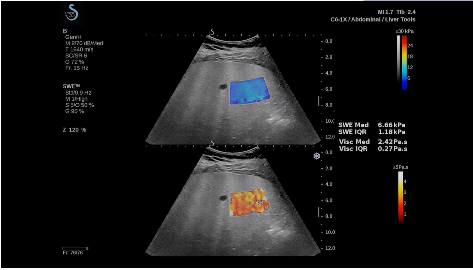

法國聲科影像(SuperSonic Imagine,SSI. Euroniex:FR0010526814)近日發(fā)表公告,宣布其研發(fā)的新一代“極速”超聲成像平臺(UltraFast Imaging),首次實現(xiàn)了肝臟的多項超聲定量評估新指標(biāo)同步檢測,包括:Att PLUS,SSp PLUS和Vi PLUS等,基本涵蓋肝臟相關(guān)病理變化指征的如纖維化、脂肪變、炎癥等。據(jù)悉,此多項新技術(shù)新將搭載于新Aixplorer系列E超系統(tǒng)。

E超相關(guān)技術(shù)已被多項多中心大樣本研究證實對于肝纖維化無創(chuàng)評估有重要意義,同時也可全面應(yīng)用于乳腺、甲狀腺、肝臟、前列腺、肌骨、婦科等全身各組織器官的定量評估和鑒別診斷。在慢性肝臟方面,聲科E超的肝臟相關(guān)定量診斷技術(shù)集,于2018年獲得美國FDA認(rèn)證,成為FDA歷史上首次獲批的單病種超聲全面定量解決方案。